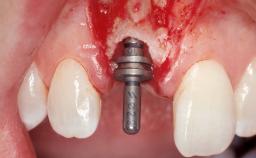

Late Flapless Placement of an Implant in a Maxillary Left Central Incisor Site

A 39-year-old male patient presented with a chief complaint of discomfort and gingival discoloration around his maxillary left central incisor. He was in good general health and was a non-smoker. His past dental history was significant because of the traumatic fracture of tooth 21 in a sporting accident at age 13. Initial dental treatment included endodontic therapy and a full-coverage restoration. The patient became symptomatic 5 years later, when structural failure of the tooth resulted in the dislodgment of the crown. Endodontic retreatment, apical surgery, and post-and-core restoration were performed.

| Type of Implants | One-Piece |

| Attachment | One-Piece |